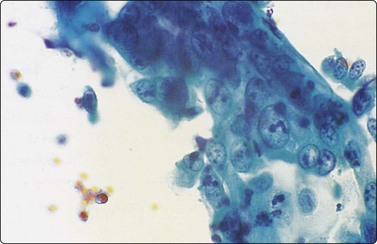

image image

Fig. 8.6 Caseation necrosis

(A) Amorphous and granular debris with neutrophils (H&E, MP); (B) Single-cell pattern of necrosis (H & E, HP).

Epithelioid histiocytes are fairly cohesive and form granulomas which are often aspirated intact (Fig. 8.5). Epithelioid cells have an elongated or bean-shaped nucleus and abundant cytoplasm which is rather pale and indistinct both in Pap- and H & E-stained specimens (Fig. 8.5). The cytoplasmic density is higher in MGG-stained material. Multinucleated histiocytes can be seen but are usually sparse. They are mainly free of intracytoplasmic pigment or birefringent material, unlike the multinucleated histiocytes seen in non-specific reactions in pulmonary tissue. Caseous necrosis has a variable appearance. There may be an amorphous to granular background with little cell outline visible, but sometimes outlines of necrotic cells may be prominent (Fig. 8.6) and often the appearances are merely of nondescript debris, histiocytes and neutrophils. Dahlgren cites granular calcific material as a common accompaniment.98 Lymphocytes may be plentiful in granulomatous inflammation.

Necrotic tumor may be homogeneous or granular and closely resemble caseous material. Conversely, we have seen cases of tuberculosis where ghost outlines of single cells were distributed across the smear and closely mimicked necrotic tumor (Fig. 8.6).

Acid-fast bacilli are more often seen in cytological material characterized by a mixture of neutrophils, histiocytes, mucoid or necrotic material than in those lesions with a prominent epithelioid cell component,99,102 though culture is positive in a similar percentage of cases with and without epithelioid cells.103 Whenever necrotic debris is seen, we restain smears with ZN stains. Maygarden described mycobacteria as negative images in a stained background in MGG material (Fig. 8.7).182 Silverman reported negative images in both Diff-Quik and Papanicolaou-stained material in a BAL sample from a patient receiving clofazimine treatment for an atypical mycobacterial infection. The reddish, refractile and polarizable drug-derived crystals can impart a pseudo-Gaucher-like appearance to the cells, simulating the negative images of an atypical mycobacterial infection.183